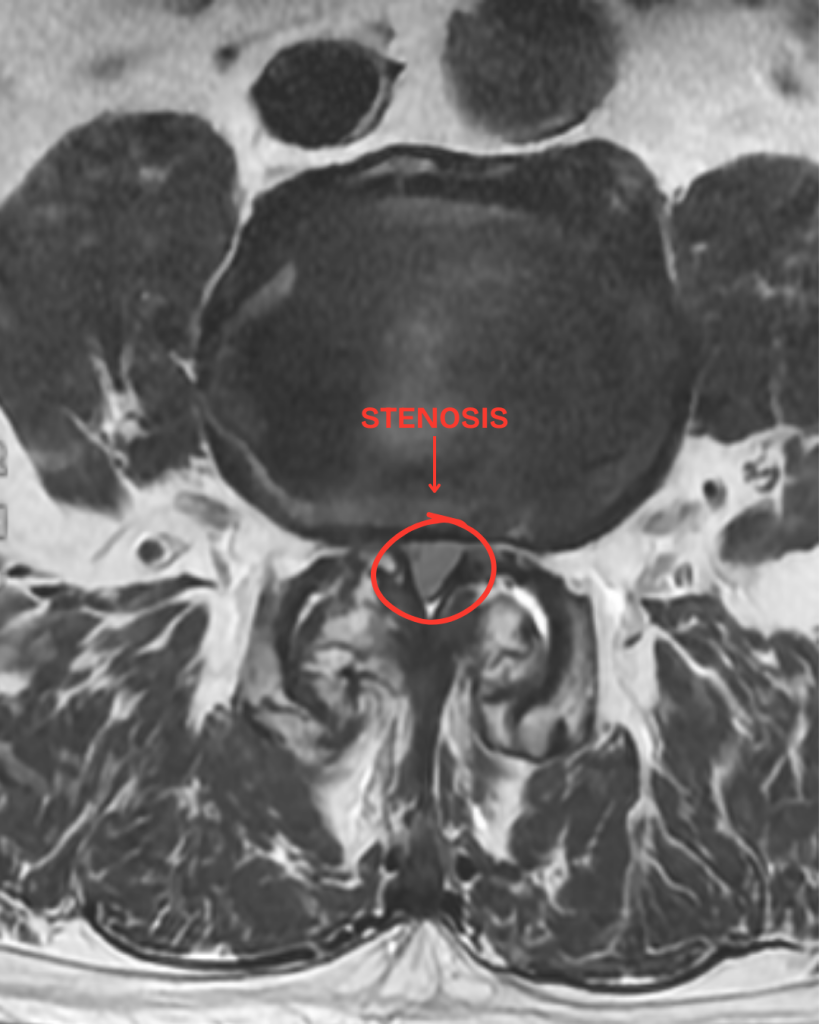

What Is Spinal Stenosis?

Spinal stenosis happens when the spaces within the spine shrink, often due to:

How Spinal Stenosis Is Diagnosed

Your doctor may use a combination of physical exams and imaging (MRI, CT, or X-ray) to confirm spinal stenosis and determine its severity.